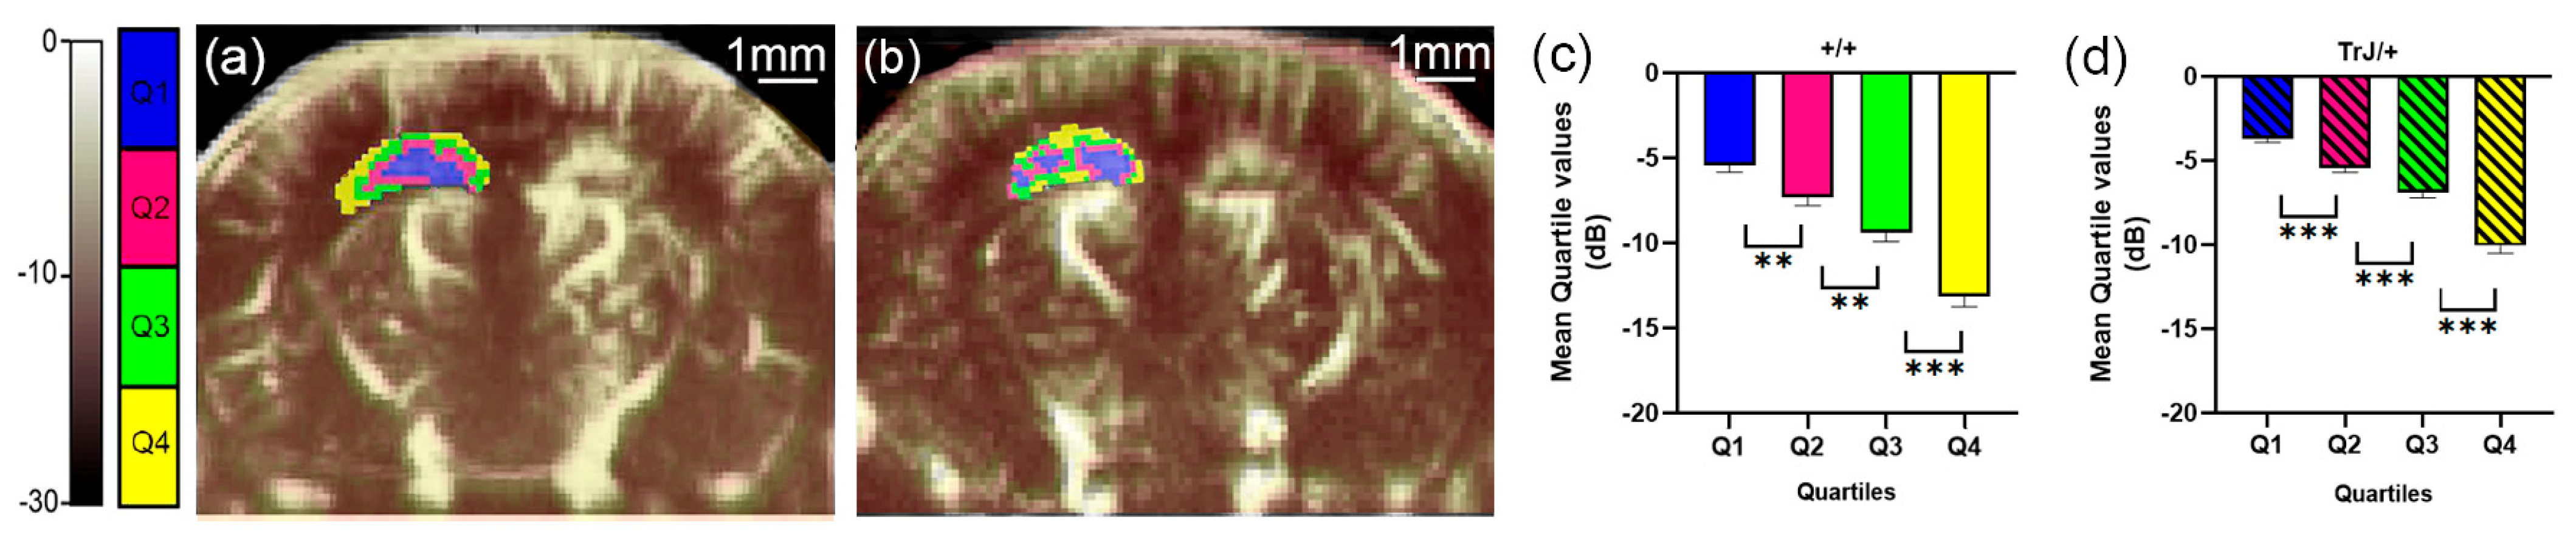

3.1. µDoppler Images Quantification

- Anzibar Fialho, M.; Vázquez Alberdi, L.; Martínez, M.; Calero, M.; Baranger, J.; Tanter, M.; Damián, J.P.; Negreira, C.; Rubido, N.; Kun, A.; et al. Intensity Distribution Segmentation in Ultrafast Doppler and Correlative Scanning Laser Confocal Microscopy for Assessing Vascular Changes Associated with Ageing in Murine Hippocampi. Sci. Rep. 2022, 12, 6784. [Google Scholar] [CrossRef]